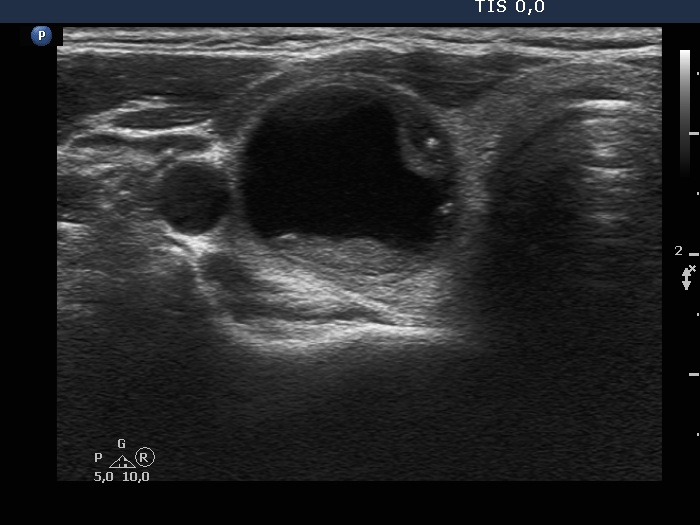

Ultrasonography. The thyroid was echonormal and had multiple moderately hypoechoic and hyperechoic nodules which showed various degrees of cystic degeneration. The largest nodule in the right lobe was dominantly cystic and presented with minimally hypoechoic solid part which included hyperechoic figures. The largest nodule in the left lobe had irregular margins.

2.5 mL cystic fluid was aspirated from the right nodule. Thereafter, the borders became irregular, lobulated. Aspiration cytology of the solid part after the removal of cystic fluid an that of the nodule having irregular borders in the left lobe resulted in bening cystic degeneration.